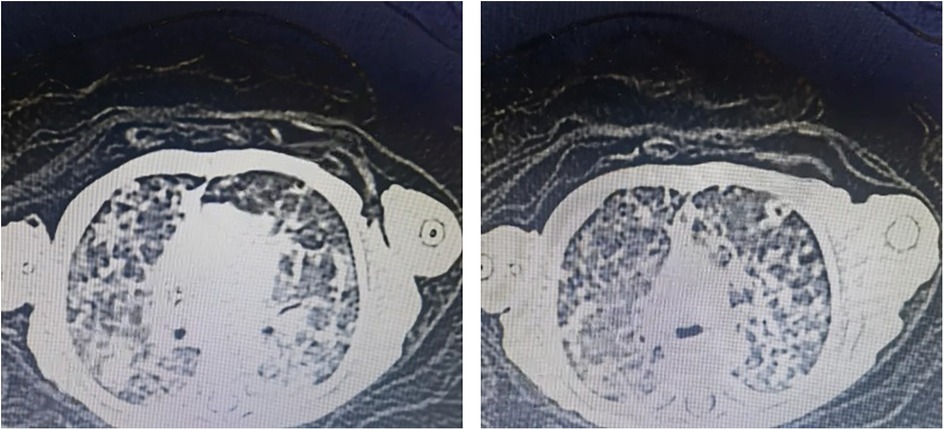

The infant had high levels of infection markers after birth, and the antibacterial treatment was not very effective, with a longer course of treatment. Blood specimen was used to perform NGS detection of M. tuberculosis complex at day 60. After the diagnosis of tuberculosis was confirmed, the antitubercular treatment was effective. CT revealed miliary TB (Figure 1).

CT scan images showing cross-sectional views of a chest, highlighting lung tissue. The left image shows dense, scattered lesions in both lungs, while the right image displays slightly more pronounced lesions. Both scans emphasize areas of concern within the lung structure.

Figure 1. CT image showing miliary TB.